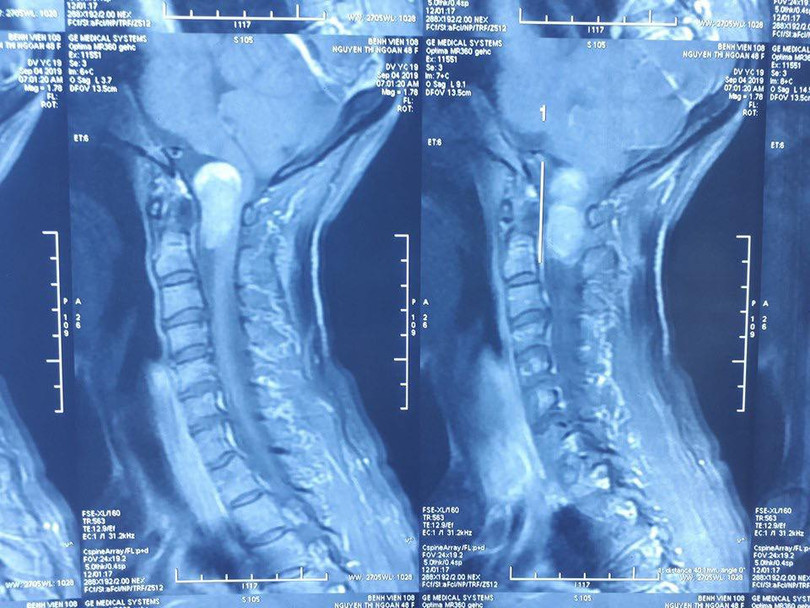

Kết quả chụp X-quang chỉ ra bà N. có khối u rễ thần kinh vùng chẩm cổ, khối u chèn ép tủy sống và hành tủy. Khối u này đã phát triển ống sống lan tỏa lên sọ não, vì vậy các bác sĩ chỉ định bà N. phải mổ ngay.

| Ảnh chụp X-quang vị trí khối u của bà N. |

Bên cạnh đó, khối u nằm ở vị trí vùng chẩm cổ - nơi có liên quan đến hô hấp, tuần hoàn - nên việc phẫu thuật rất khó khăn. Các bác sĩ phải khéo léo để loại bỏ hoàn toàn khối u, đồng thời đảm bảo không xảy ra biến chứng suy hô hấp cho bệnh nhân.

Nỗ lực của các bác sĩ đã thành công, khi loại bỏ hoàn toàn khối u ở vùng chẩm cổ có kích thức 3x2cm, giúp bà N. không còn phải chịu đựng ảnh hưởng xấu của khối u quái ác.